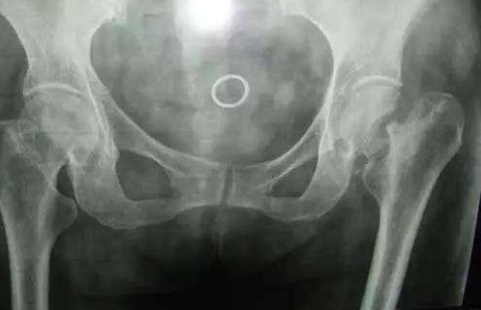

河南骨科专科医院:股骨头坏死关节置换的使用年限是

河南骨科专科医院介绍股骨头坏死是骨科比较常见的一种疾病,这种疾病发生以后,如果骨头已…[详情]